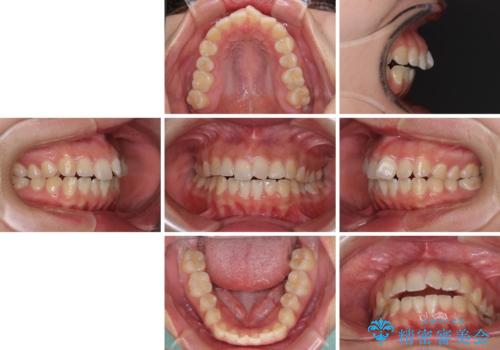

- 上下の前歯が非接触であることと、それに伴う口元の閉じにくさを気にして来院された患者様です。

奥歯の咬み合わせを見ると、上顎が下顎に対して相対的に前方にありました。

口元の閉じにくさを改善するためには、上顎臼歯を後方に移動させた咬み合わせにする必要があります。

インビザライン単体で改善することも可能ですが、達成する可能性が高くないため、カリエールディスタライザーという補助装置を併用して、より確実性を上げることとしました。

奥歯の咬み合わせを改善しながら、並行してインビザラインで歯列を整えることとしました。